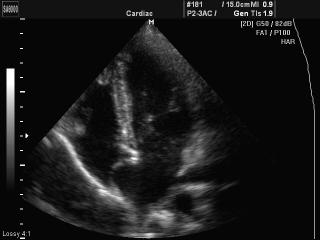

Heart (short & long axis of the LV), B-mode

MySono-U6. Heart (short & long axis of the LV), B-mode.